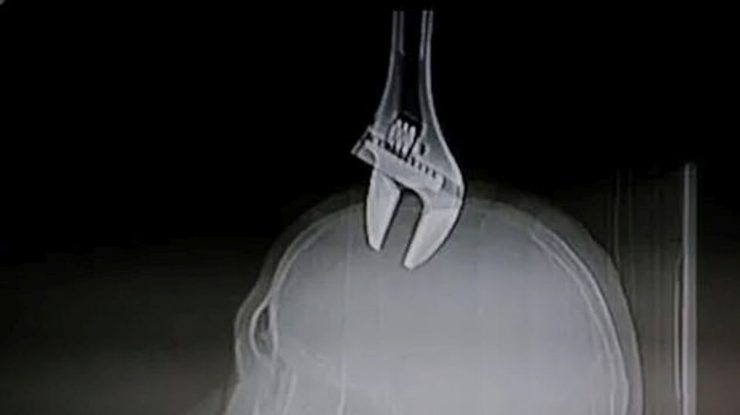

- Unui chinez de 50 de ani i s-a înfipt în cap o cheie franceză de 15 centimetri.

- Medicii l-au operat timp de trei ore pentru a-i scoate obiectul.

- Bărbatul a supraviețuit datorită oaselor craniene foarte groase.

Un chinez în vârstă de 50 de ani a supraviețuit după ce i s-a înfipt în cap o cheie franceză de 15 centimetri, relatează Daily Mail.

Unealta a fost scăpată de un muncitor care instala un aer condiționat pe un bloc de 8 etaje.

Medicii i-au scos victimei obiectul din cap, iar operația a durat trei ore. Bărbatul se simte bine, după toate cele întâmplate.

După o operație de trei ore, medicii au scos obiectul din capul pacientului, acesta aflându-se în stare stabilă. Bărbatul a rămas internat în spital.

„Pacientul are un trup puternic și un craniu foarte gros. Prin urmare, unealta nu a pătruns foarte adânc. Ar fi fost mult mai periculos dacă în locul lui se afla o femeie sau un copil”, a explicat un doctor.